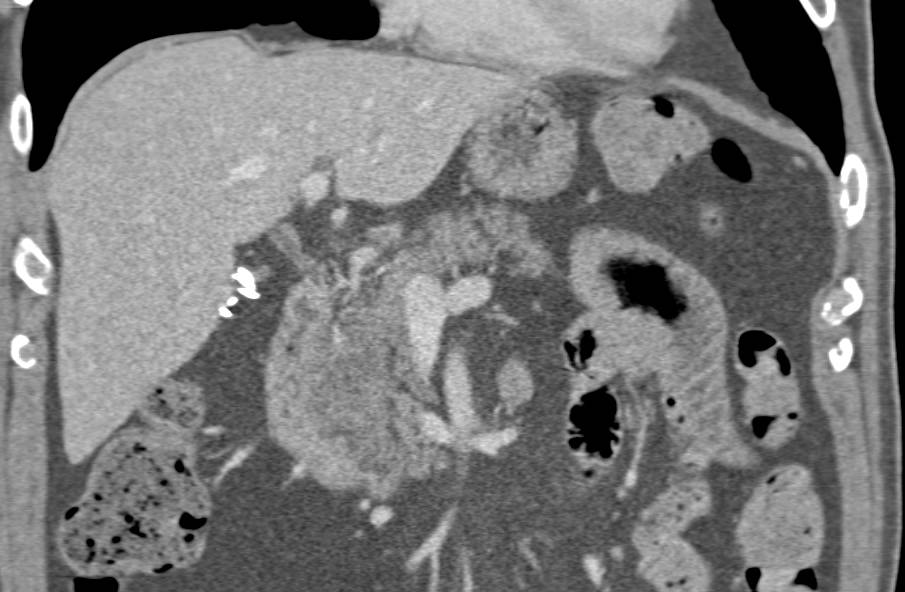

Fatty Infiltration of the Head of the Pancreas